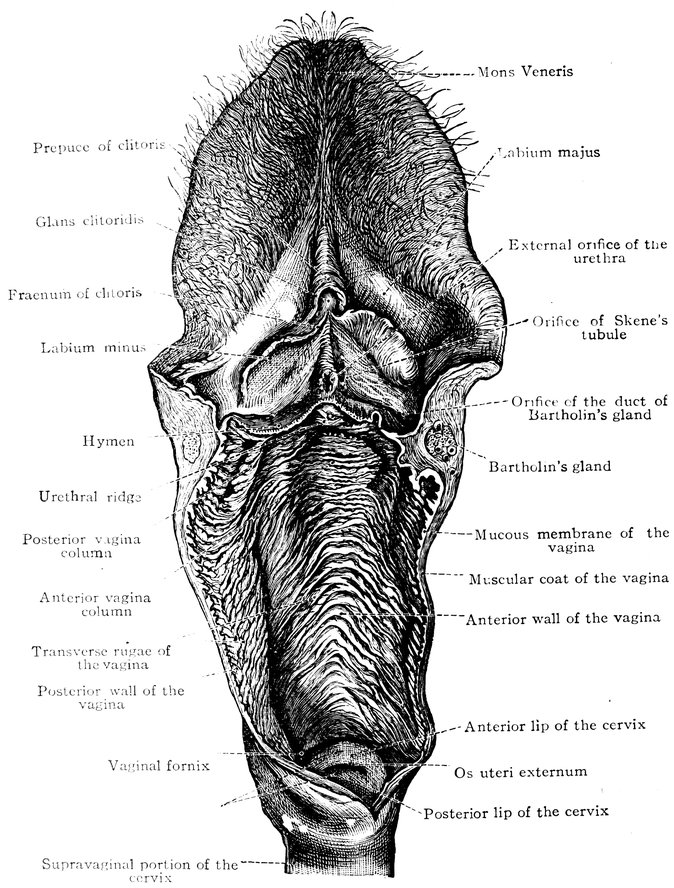

| 48. | The female pudendum, or vulva, with the labia majora | 204 |

| 49. | Vestibule of the vagina, with the labia minora or nymphæ, etc | 205 |